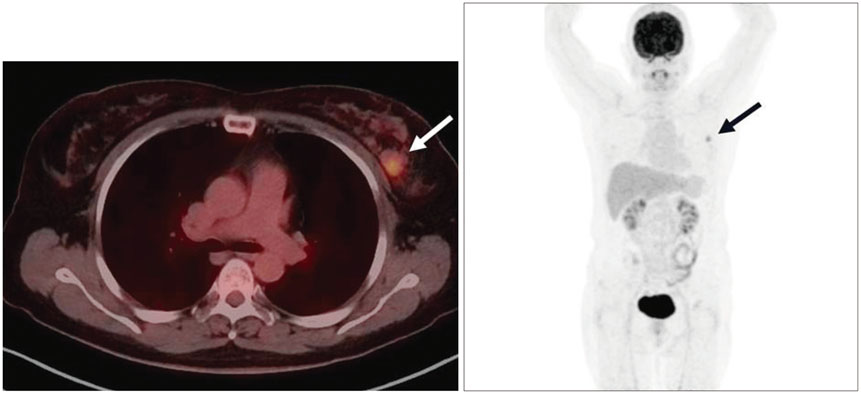

Radiologic and Pathological Correlation of Adenoid Cystic Carcinoma of the Breast: A Case Report

- Adenoid cystic carcinoma (ACC) is a subtype of adenocarcinoma that is usually seen in the salivary glands. It has also been reported in other organs including the breast, skin, tracheobronchial tree, cervix, larynx, and Bartholin gland. ACC in the breast is rare, accounting for less than 0.1% of all breast cancers. Furthermore, the imaging characteristics of ACC of the breast have not been well described in the literature, especially regarding the findings with magnetic resonance imaging (MRI). Here, we report radiologic findings of a rare case of ACC in the breast by mammography, sonography, computed tomography (CT), positron emission tomography/CT, and MRI with pathologic correlation and a review of the literature.